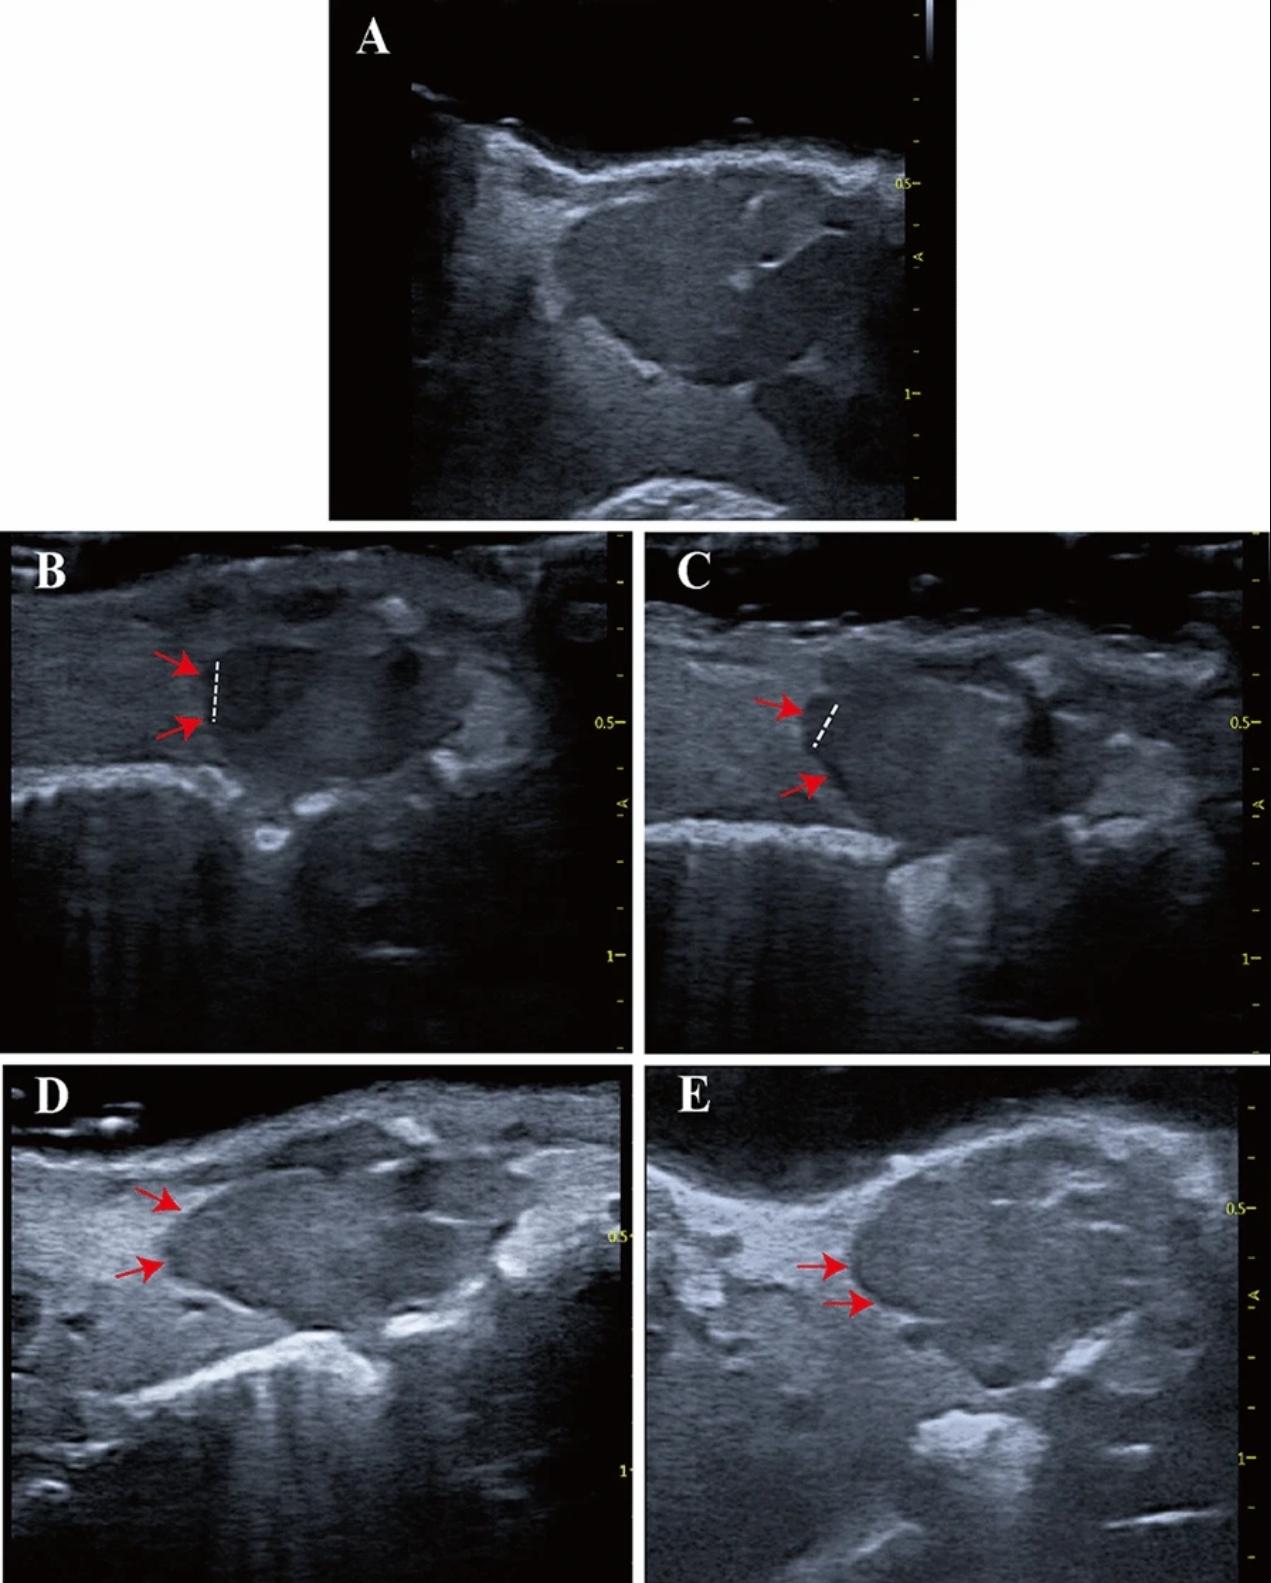

Fig. 3 Echocardiographic imaging can monitor regeneration of X. tropicalis injured hearts in a scar-free manner. A: Representative echocardiography image of the same-age nonapical resection group under B-mode. B: Representative image 5 days after apical resection. The damaged heart with a missing apex (left side of the dashed line) was clearly identified under echocardiography. C: Representative image 10 days after apical resection. D: Representative image 30 days after apical resection. E: Representative image 45 days after apical resection. The regeneration of the injured heart was able to be monitored and justified dynamically by the recovery of morphology and anatomic structure under echocardiographic imaging at 5 days, 10 days, 30 days and 45 days after apical resection. The boundary between the apical region of the regenerated heart and the surrounding tissue was clear, and no adhesion with the surrounding tissue was found at 30 days and 45 days after apical resection. Red arrow: Area of the boundary between the apical region of the regenerated heart and the surrounding tissue. Dashed line: Boundary of the regeneration zone and noninjury zone